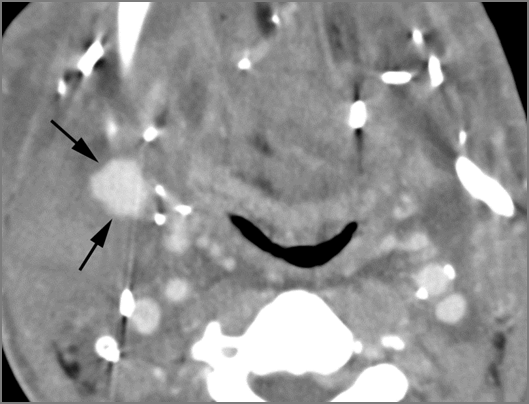

If there is suppurative cervical adenopathy the purulent material outside the lymph node(s) capsule(s).